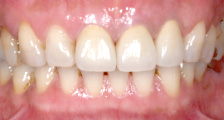

オールセラミック クラウン症例

すべてが白いセラミック(陶材)でできています。自然なツヤがあり光を通すので、口元に明るい印象を与え、美しい仕上がりが期待できます。

(歯の土台は光透過性のあるグラスファイバーで作成します。)